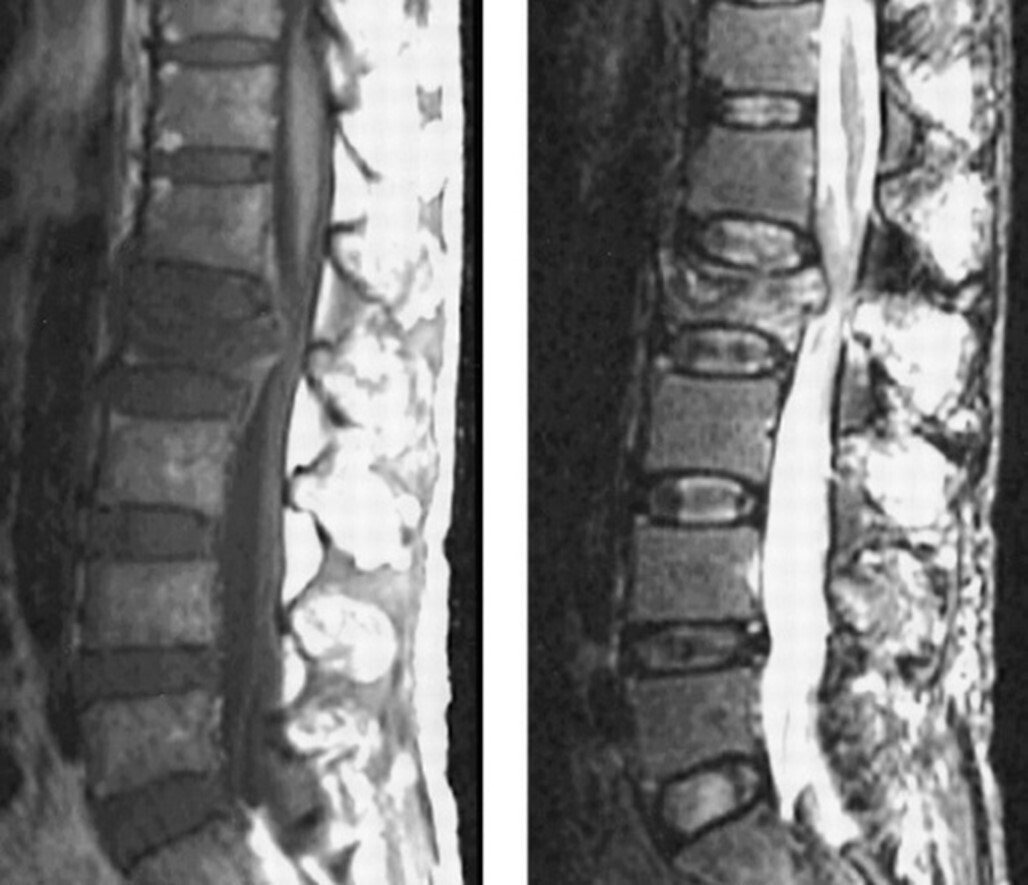

En cas de métastases osseuses symptomatiques, un bilan couplant IRM et scanner est souvent nécessaire avant toute décision chirurgicale ou de radiothérapie. La TDM permet un bon bilan osseux et l’IRM visualise les lésions des parties molles et les rapports avec la moelle, la queue de cheval ou les racines nerveuses. L’IRM permettra également de visualiser une prise de contraste de la dure-mère évocatrice d’épidurite qui sera à irradier ou à opérer si elle est symptomatique.

Le patient bénéficie d’une imagerie par scanner du rachis.

Question 4 - En interprétant ces images, vous notez (une ou plusieurs réponses correctes) :

Non visible ici, en revanche il existe des hernies intraspongieuses qui ont une origine mécanique.

Notamment au niveau sacré et L2.

Vide discal (pincement), géodes, ostéophytes et ostéocondensation sous chondrale.

Image lytique en miroir non visible ici, en revanche il existe des hernies intraspongieuses qui ont une origine mécanique.

Le cancer de la prostate métastatique se présente classiquement par une atteinte ganglionnaire et/ou osseuse.

D’autres localisations plus rares sont possibles et de moins bon pronostic : hépatiques, pulmonaires, cérébro-méningées.

Les métastases osseuses peuvent être ostéolytiques et/ou ostéocondensantes (caractéristique assez spécifique, avec possible vertèbre ivoire).

Vous réalisez une TDM et une IRM rachidienne qui retrouvent des lésions osseuses ostéocondensantes du rachis lombaire et sacrées sans retentissement neurologique. Le PSA sérique total est à 700 ng/mL. Vous suspectez un cancer prostatique métastatique.

Question 9 - Votre analyse de l’IRM retrouve (une ou plusieurs réponses exactes) :

Le tableau neurologique est lié au recul du mur postérieur qui comprime les parties molles (le fourreau dural et les racines de la queue de cheval au niveau de L2). Il s’agit donc à ce niveau-là d’une compression de racines périphériques expliquant l’abolition des réflexes et le syndrome de la queue de cheval. À l’inverse, un syndrome pyramidal est observé en cas de compression médullaire, et donc de la moelle épinière située au-dessus de L1, par exemple en cas d’atteinte des vertèbres dorsales ou cervicales. Le recul du mur postérieur et le contexte vont contre une origine ostéoporotique. Il n’y a pas d’anomalie visible des racines en dehors de la compression de niveau L2.

Vous suspectez une complication rachidienne avec fracture de L2 et recul du mur postérieur responsable d’un syndrome de la queue de cheval.